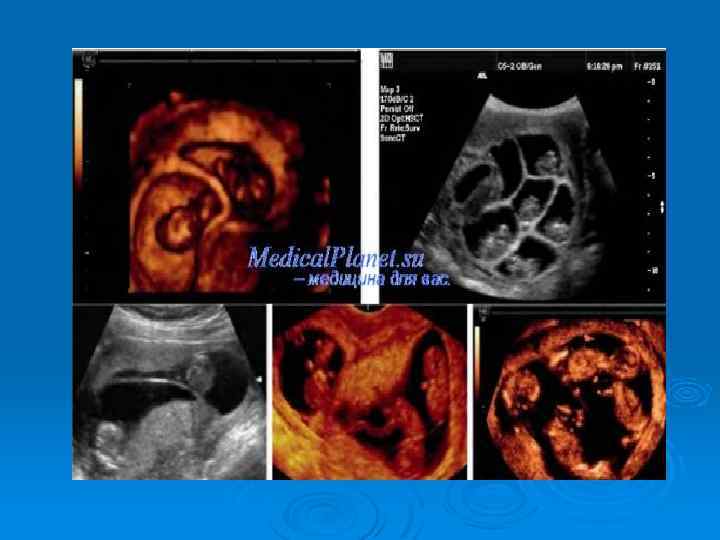

-Достоверные признаки многоплодной беременности выявляются при ультразвуковом исследовании, позволяющем определить многоплодную беременность, начиная с первой ее половины. - Для диагностики многоплодной беременности применяют фоноэлектрокардиографию, при помощи которой можно зарегистрировать сердечные тоны близнецов не только в последние месяцы беременности, но также в срок 20— 22 недели и ранее.